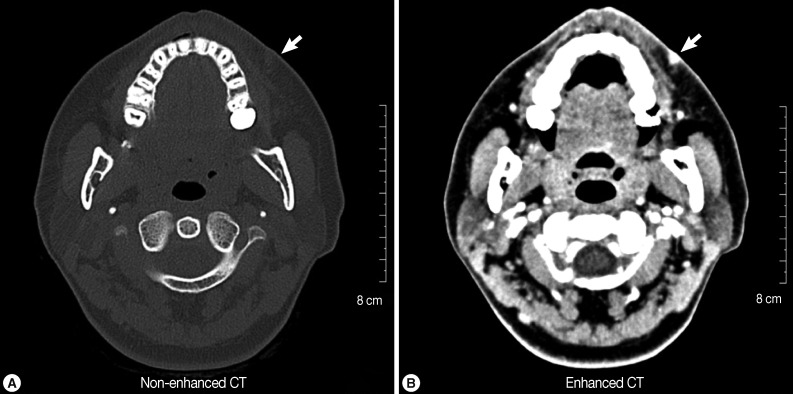

The patient was a 32-year-old Korean woman who was working as a cashier in a Korean restaurant in the suburb of Seoul, Republic of Korea. In August 2011, she sensed a small mass in her left nasolabial fold area of the face before being seen at the Department of Plastic and Reconstructive Surgery, Bundang Jesaeng General Hospital, Bundang, Korea. She experienced painful swelling and itching several times, with signs of migration, but there were no other symptoms, such as fever and chill. On physical examination, a small nodule about 1 cm in diameter was noted. At that time, she did not receive any special treatment for the mass. In August 2012, she had CT scans (non-enhanced and enhanced) on the soft tissues of the left nasolabial fold area, where a small mass with high density was recognized on the external side (Fig. 1A, B). Two weeks later, the swelling had moved slightly to the mucosal area of the upper lip, and we decided to surgically remove the lesion in September 2012. Serological tests were performed to check for 4 kinds of anti-parasitic antibodies (Clonorchis sinensis, sparganum, cysticercus, and Paragonimus westermani) with negative results.